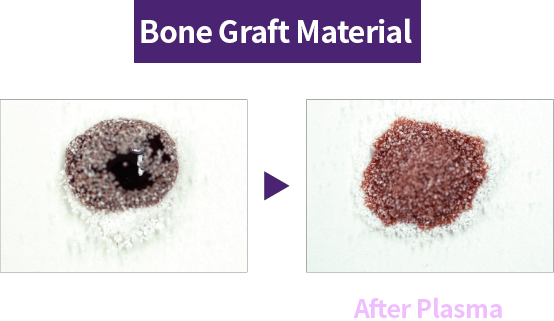

During manufacturing, shipping, and long-term storage, hydrocarbons can accumulate on the implant surface, reducing biocompatibility. Plasma implants remove hydrocarbons with high-energy plasma and reactivate the surface for higher biocompatibility.

Plasma treatment helps remove impurities left on the implant surface and improves surface hydrophilicity for better biocompatibility. Thanks to these benefits, plasma technology helps improve implant success and serves as a key factor for faster recovery.

Creating a safer implant surface through removal of surface impurities

Improved early protein attachment through organic removal and surface activation